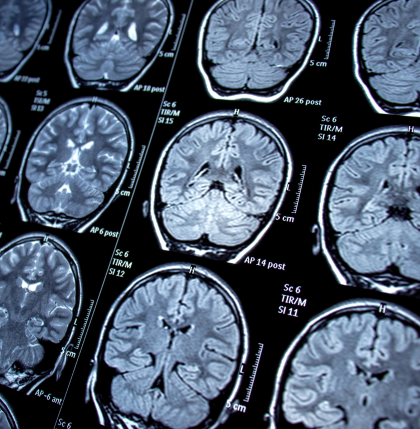

4. Diagnostic Tests and Imaging

While there is no single test that definitively diagnoses Parkinson’s, doctors may use imaging to support their evaluation:

• DaTscan: Helps visualize dopamine function in the brain

• MRI or CT scans: Used to rule out other conditions with similar symptoms

Laboratory tests can also rule out metabolic or endocrine disorders that mimic PD.